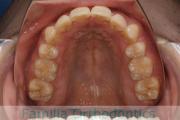

No.22V-104

- 主な症状:

- 側方偏位

- その他の症状:

- 叢生

- 年齢:

- 19歳

- 性別:

- 女性

- 主な使用装置:

- FEA

- 治療にかかった費用:

- 90万円

歯並びを綺麗にしたいということで来院されました。叢生(でこぼこ、凹凸、ガタガタ)と上下顎前突のため、上下左右から小臼歯を抜歯の上で、歯科矯正用アンカースクリューを併用したマルチブラケット法を行いました。約2年半、30回の通院が必要でした。

上下とも叢生がありますので、後戻りのリスクがあります。